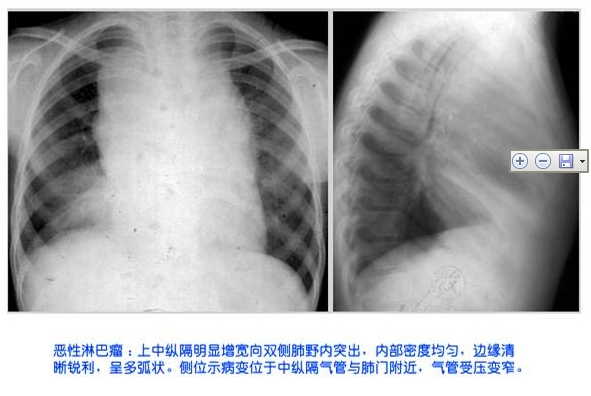

照片名称:恶性淋巴瘤x射线